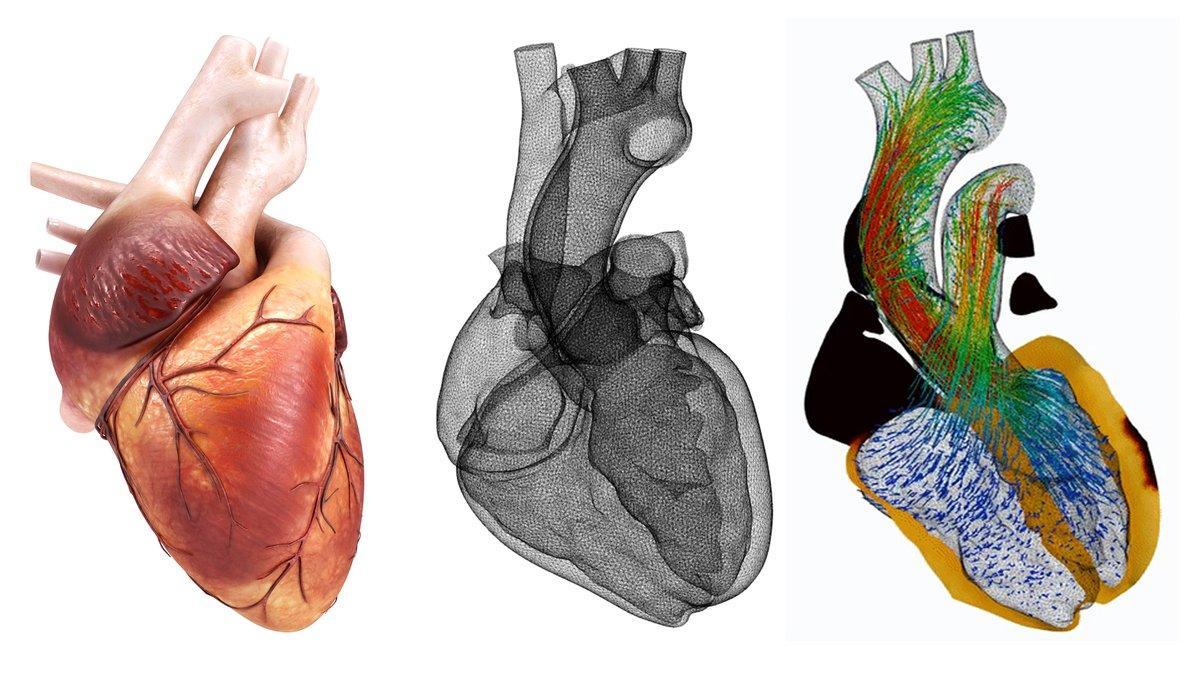

corazon-supercomputador / ALYA RED

Como si de un problema de ingeniería se tratara, el equipo responsable del corazón virtual ha abordado el reto descomponiendo su estudio en varios problemas, solucionando cada uno de ellos de manera individual para posteriormente volver a ensamblar una imagen conjunta del órgano. El corazón, al fin y al cabo, no es más que músculo, sangre y electricidad funcionando como uno de los mayores misterios de la anatomía. De ahí que se necesiten más de 200 procesadores y cinco horas para ejecutar su simulación, una tarea tan solo posible con un superordenador.